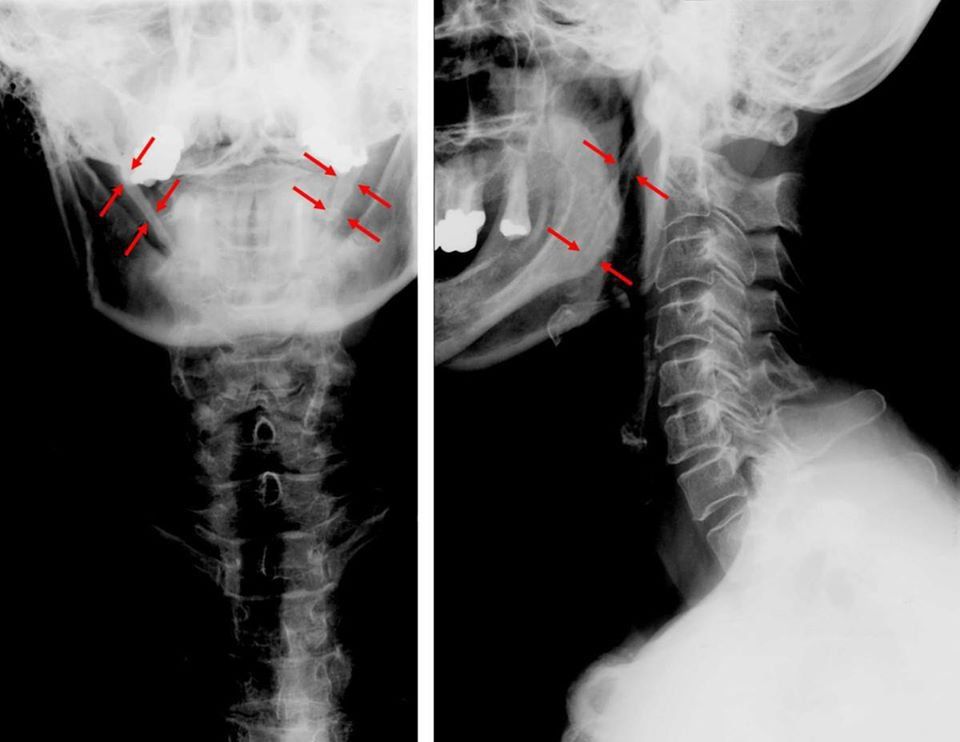

Kỹ thuật chụp Xquang mỏm trâm

Ở cơ thể người, mỏm trâm chính là mỏm xương một đầu gắn vào xương thái dương, mỏm trâm bình thường sẽ có chiều dài dưới 2,5cm, trường hợp dài trên 3cm thì bị coi là dài mỏm trâm.

Dài mỏm trâm là hiện tượng mỏm trâm bị dài ra quá mức cho phép và gây ra những sự khó chịu nhất định cho người bệnh tại vùng họng và tai. Bệnh dài mỏm trâm được mô tả lần đầu vào năm 1937 bởi bác sĩ Watt Eagle, dấu hiệu dài mỏm trâm thường thấy ở người bệnh chính là nuốt vướng, nuốt đau, sờ hố Amidan thấy đầu mỏm trâm.

Bước 2: Người bệnh nằm tư thế ngửa trên bàn chụp X quang sao cho mặt phẳng chính diện vuông góc với phim và 2 tay duỗi thẳng thật thoải mái. Đường nhân trung và lỗ tai vuông góc với phim, người bệnh há miệng. Trong trường hợp nằm sấp thì 2 tay phải gập và chống lên mặt bàn.